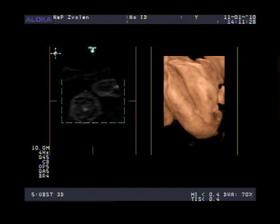

- 19.2.10 sono v 30tt , pani doktorka nas pozrela od hlavy po paty a vsetko je tak ako ma, skontrolovala aj prietoky a su na vybornu a vazime 1670g a

mame na 100% potvrdene DIEVČATKO 🙂.....